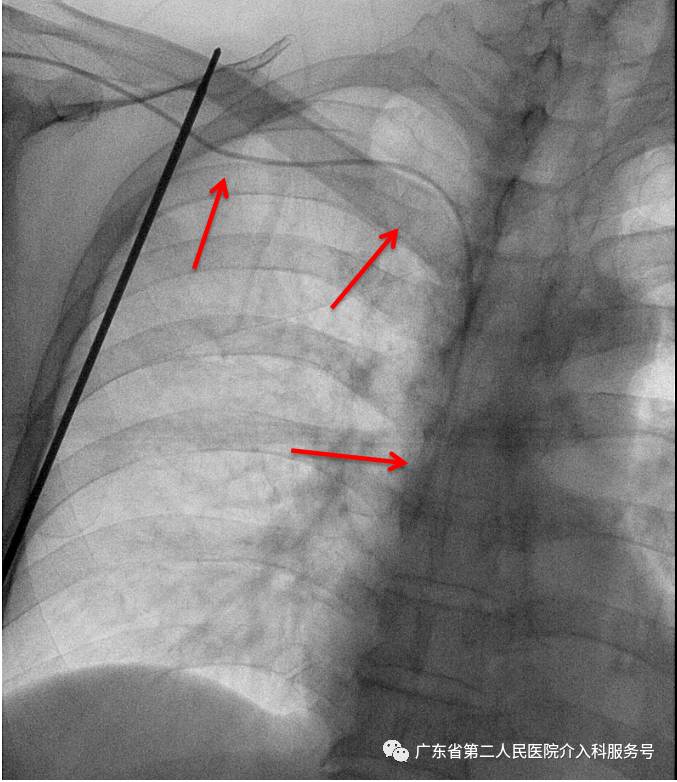

C.建好皮下隧道时,可透视调整导管远端在下腔静脉内的深度(常为T5~T7之间)